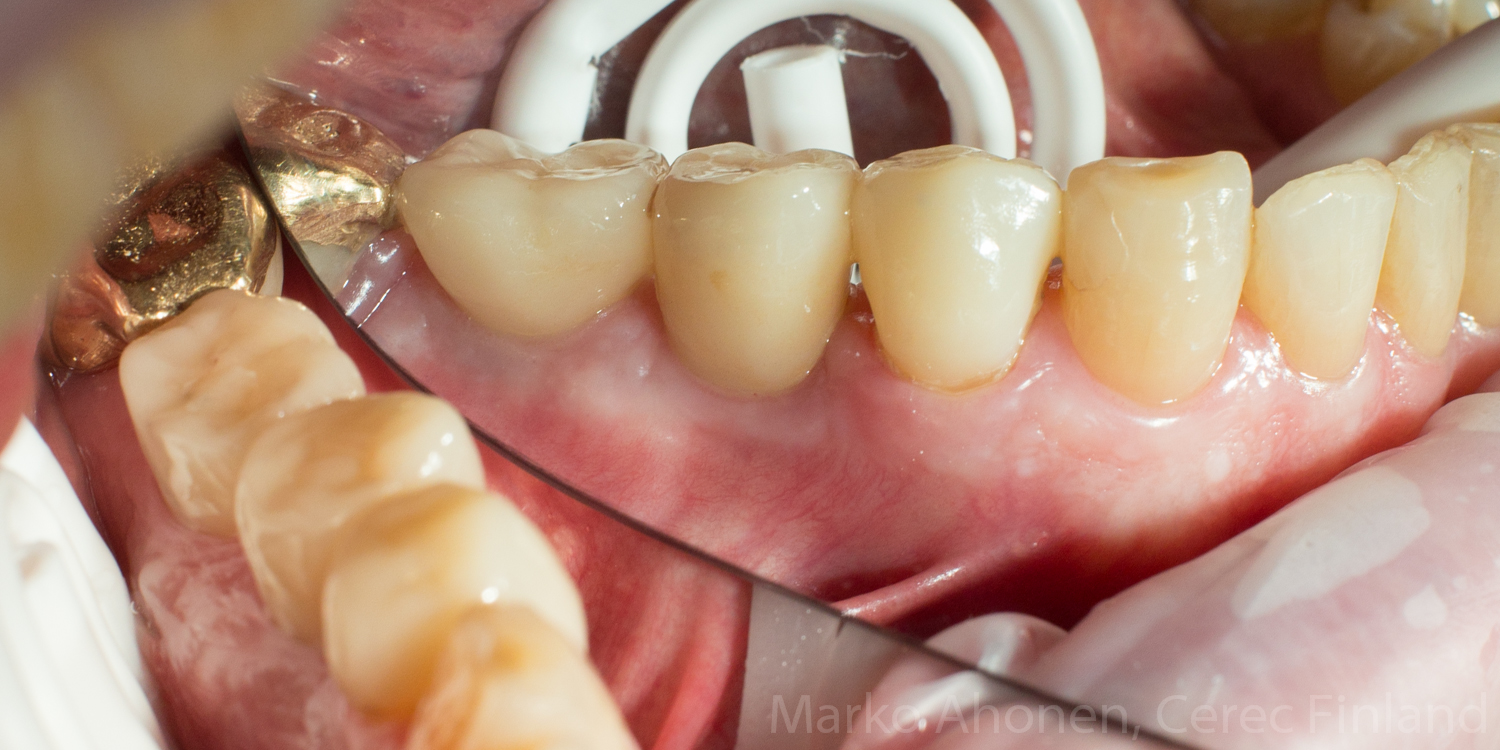

Valmiit implantit ja kruunu suussa (kontrolli 1kk hoidosta):

IMG_6352 IMG_6343 IMG_6349 IMG_6358